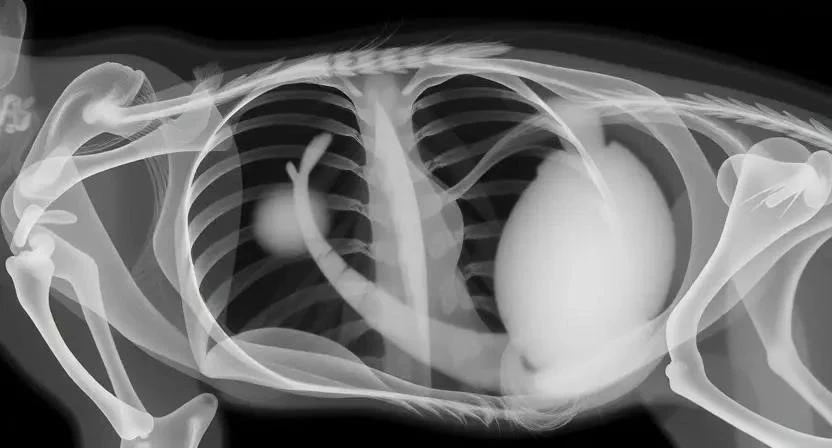

Диагностика рака у кошек – это многоэтапный процесс, направленный на точное определение типа опухоли и стадии заболевания. Ветеринар проведет клинический осмотр, назначит анализы крови, рентген, УЗИ, биопсию, КТ или МРТ. Анализы крови помогут оценить общее состояние организма и выявить признаки воспаления или инфекции. Рентген и УЗИ позволяют визуализировать внутренние органы и обнаружить опухоли. Биопсия – это взятие образца ткани для исследования под микроскопом, что позволяет точно определить тип рака. КТ и МРТ предоставляют более детальные изображения внутренних органов.